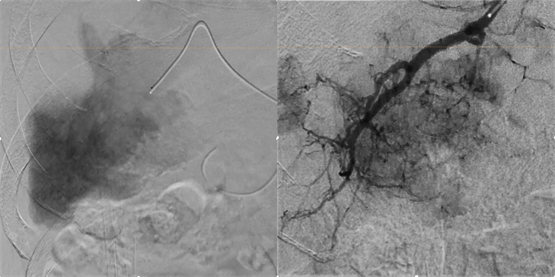

左图(Hi-def Mode 2.3 inch):显示范围更广,能直观看到肝脏整体血供与病灶分布,但细微动脉分支显示有限。右图(Hi-def Mode 3 inch):在更高分辨率下,供血动脉走向、分支细节、瘤体灌注清晰可见,病灶供血结构完整呈现,便于医生精确定位靶血管并实施“超选插管”栓塞。

得益于显微高清模式,Sky+正突破边界,赋能精细化的肝癌介入。在肝癌TACE介入治疗中,传统影像模式下往往难以清晰识别靶血管及瘤体灌注范围,容易出现栓塞不全或误栓正常肝组织的风险。显微高清模式通过提升空间分辨率与对比分辨率,使微小血管走向、瘤体供血及导管末端位置清晰可见,帮助医生在术中精准识别并超选插管至肿瘤供血动脉分支,实现更彻底、更安全的靶向栓塞。